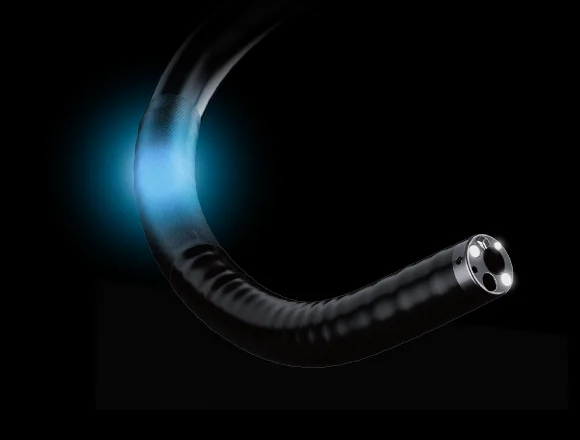

3 Световода

Инновационная система подсветки тремя светододами на дистальном конце обеспечивает более масштабное и равномерное освещение во время проводения процедур. В сочетании с широким полем обзора это обеспечивает высочайшее качество изображения.